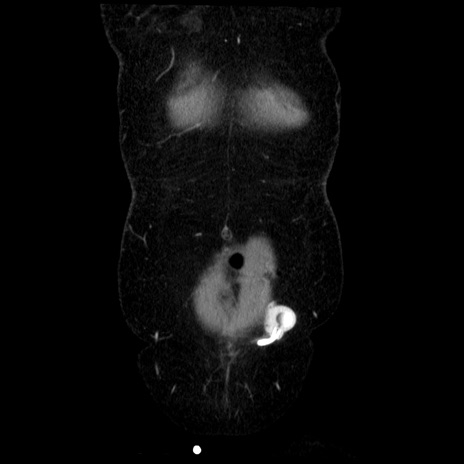

症例6(冠状断像)

【症例】50歳代女性

【主訴】下腹部痛

【現病歴】本日朝より下痢2回あり。 昼食を食べた後、嘔吐3回、下腹部痛認め、症状軽快せず、当院救急搬送。

最終食事:本日昼(生ものなし)。 昨日の夜、刺身を食ぺたとのこと。周囲に同様の症状の者なし。普段、排便は毎日あるとのこと。

【既往歴】卵巣癌術後(8年前に当院で卵巣摘出)

【身体所見】 意識清明、腹部:平坦、腸蠕動音→、やや硬、下腹部自発痛・圧痛あり、反跳痛あり、筋性防御なし。

【データ】WBC 16000、CRP 0.01